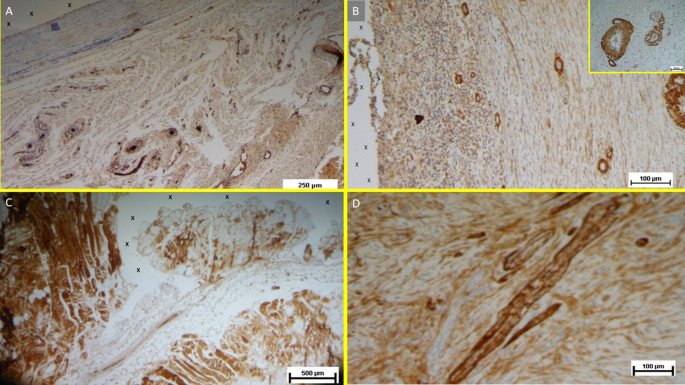

Vascular Growth Factors: Early VEGF-induced neovascularization (Fig. 11D) transitioned to a predominance of CD31-positive endothelial cells in the midterm, along with SMA-driven vascular maturation (Fig. 12A). Long-term specimens exhibited further SMA-mediated structural thickening, with complete vascular development (Fig. 12B).

(A) Tissue sample removed from the 3D scaffold of the S&D device six months implantation. Numerous clusters of intense neo-angiogenesis (colored in brown) with well-developed vascular structures are clearly evident close to the device fabric (X). CD31 50X—(B) Tissue sample excised from the 3D scaffold of the S&S device 8 months post-surgery. Numerous venous elements showing well-constituted muscular layer are highlighted close to the scaffold fabric (X). SMA 100X—The high magnification microphotograph in the right upper corner depicts two arterial structures with a well-represented muscular layer (colored in brown). SMA 200X—(C) Biopsy sample excised from the scaffold of the S&S device 6 months post implantation. The image shows plenty of muscular elements (colored in brown) grouped in bundles close to the TPE structure of the device. NGF 25X—(D) Biopsy specimen excised from the 3D scaffold of the S&S device 6 months post-implantation. The image shows a mature elongated nervous structure (colored in brown) developed within the TPE scaffold. NGFRp75 100X.